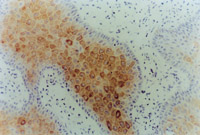

MEBT/MEBO治療30天后,再生修復的上皮組織進行細胞角質素AE3檢查為陽性,表皮顆粒層細胞質呈棕色染色,細胞核呈藍色(圖5-3-9~5-3-6),證實為自身再生的復層鱗狀上皮。

5-3-9 MEBT/MEBO治療30天,細胞角質素AE3呈陽性。(說明患者燒傷創(chuàng)面是自我再生修復) HE×20

5-3-10 同上  HE×40